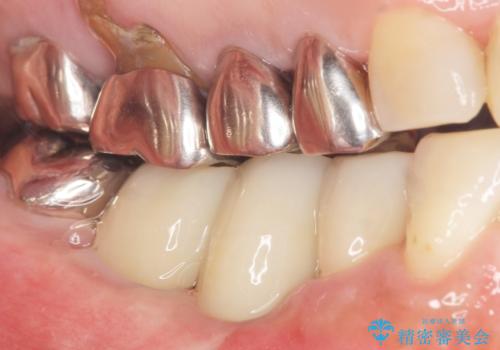

奥歯でしっかり咬むことができるようになり、大変喜んで頂けました。

クラウンの種類:オールセラミッククラウン ベレッツァ

- ¥1,177,000 (根管治療、土台、骨増生、インプラント・アバットメント×2本、仮歯・クラウン×3本) ※税込費用は治療当時の料金となります